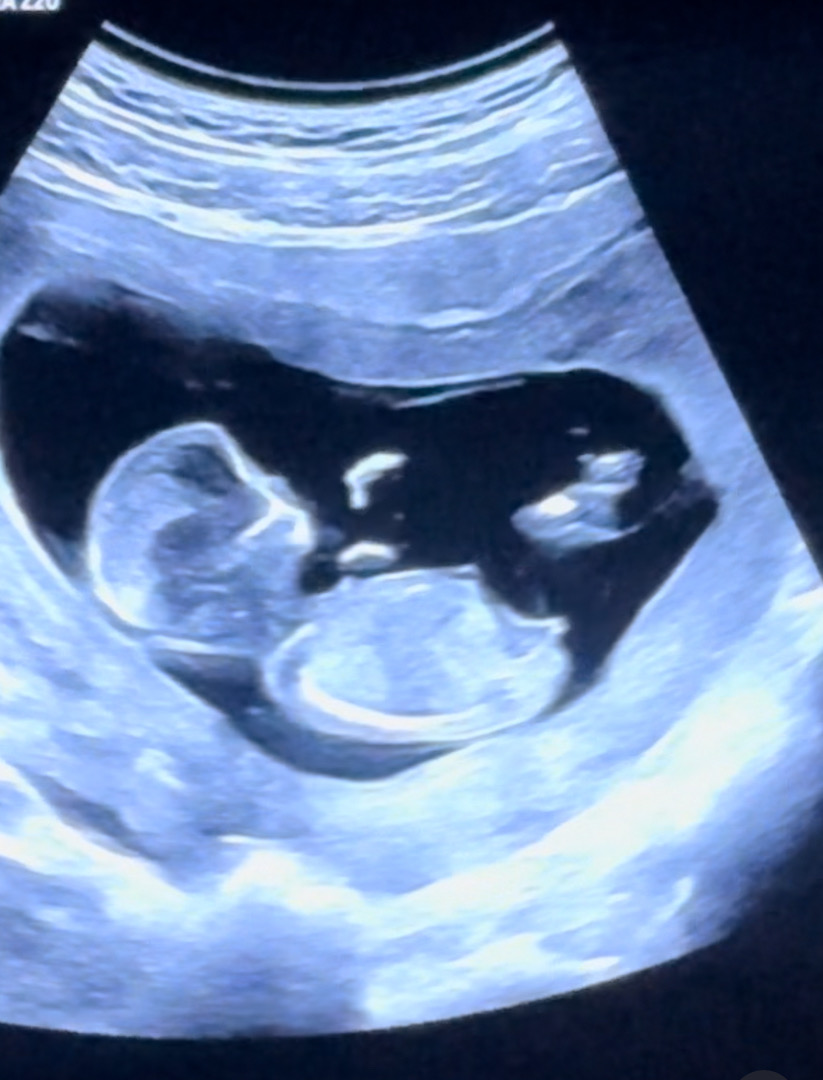

각도법 참견 부탁드려용 ㅎㅎ🙏🏻

12주 1일이에요!

잘 안보이지만 딸같아요